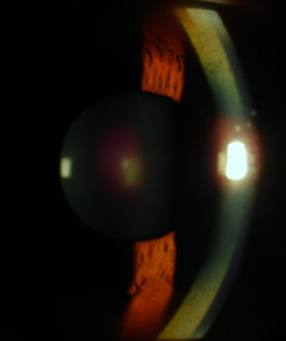

裂隙灯检查下的K-F环

肝豆核状变性是一种先天性铜代谢障碍性疾病。K-F环,是由于铜无法正常代谢,而逐渐沉积于角膜后弹力层后形成的。早期可通过裂隙灯检查发现。